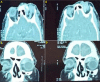

Masson tumor is a benign vascular lesion characterized by an intravascular papillary endothelial hyperplasia. Peri orbital locations are rare. We report a case of Masson tumor localized in the upper internal angle of the left orbit revealed by progressive ocular proptosis. Orbital computed tomography (CT) scan and magnetic resonance imaging (MRI) showed a vascular mass in the left internal canthus mimicking an arterioveinous malformation. The patient underwent total removal of the lesion with a favorable postoperative follow up. Histological examination found an intravascular papillary endothelial hyperplasia without atypical features corresponding to Masson tumor. A thorough literature review of Masson tumor is presented with a discussion of clinical findings and management.